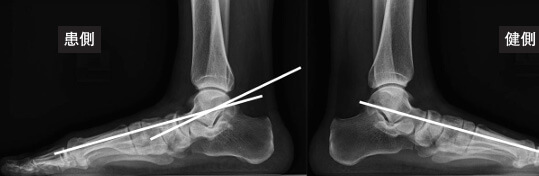

■側面から

距骨-第1中足骨角(LTMT)という角度を測ります。

これも詳細な説明は省きますが、正常が一本線、2本が混じるときに角度の差が10度以上の差が足の甲側か足底側に出るかによって評価します。扁平足か、凹足(アーチが高い)かを判断します。

参照画像元:秋山 唯、日本フットケア・足病医学会誌4(1):17-21,2023